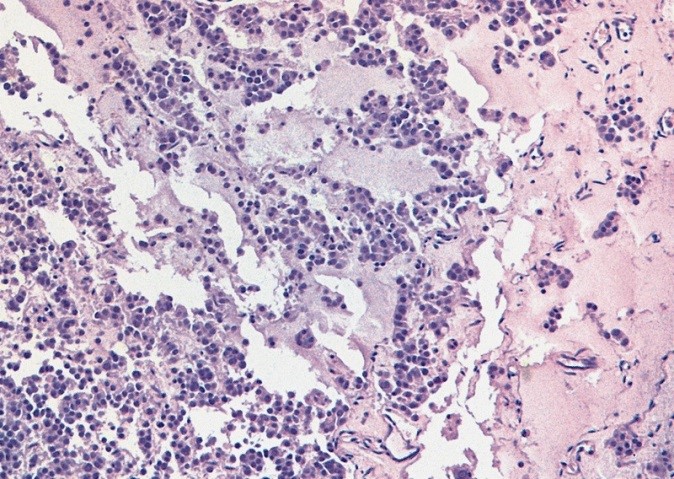

Микропрепарат, семинома

02.jpg